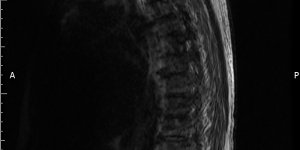

Back Pain | Ankylosing Spondylitis | Cases

26 ♂ Presented to MSK service with back pain. Gave a 7 year history of back pain (started aged 19) Seen previously in MSK service 5 years ago (aged 21). Had an MRI scan which was normal. Has has physiotherapy in the past. Has been regularly having chiropractic treatment. Reports that his back remains arched when he is lying supine (lordosis [...] Read more